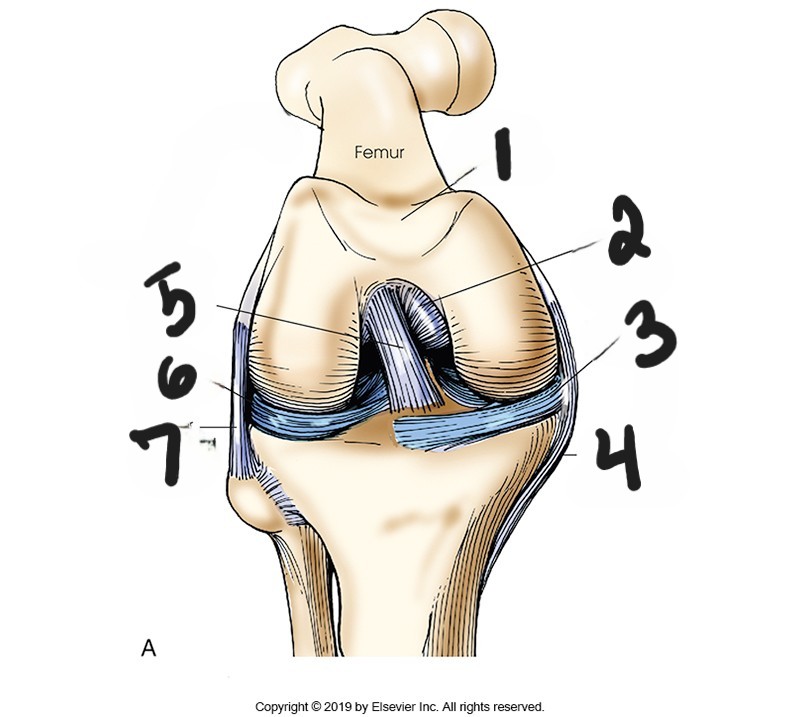

patellar surface

what is #1?

posterior cruciate ligament

what is #2?

medial meniscus

what is #3?

tibal collateral ligament

what is #4?

anterior cruciate ligament

what is #5?

lateral meniscus

what is #6?

fibular collateral ligament

what is #7?